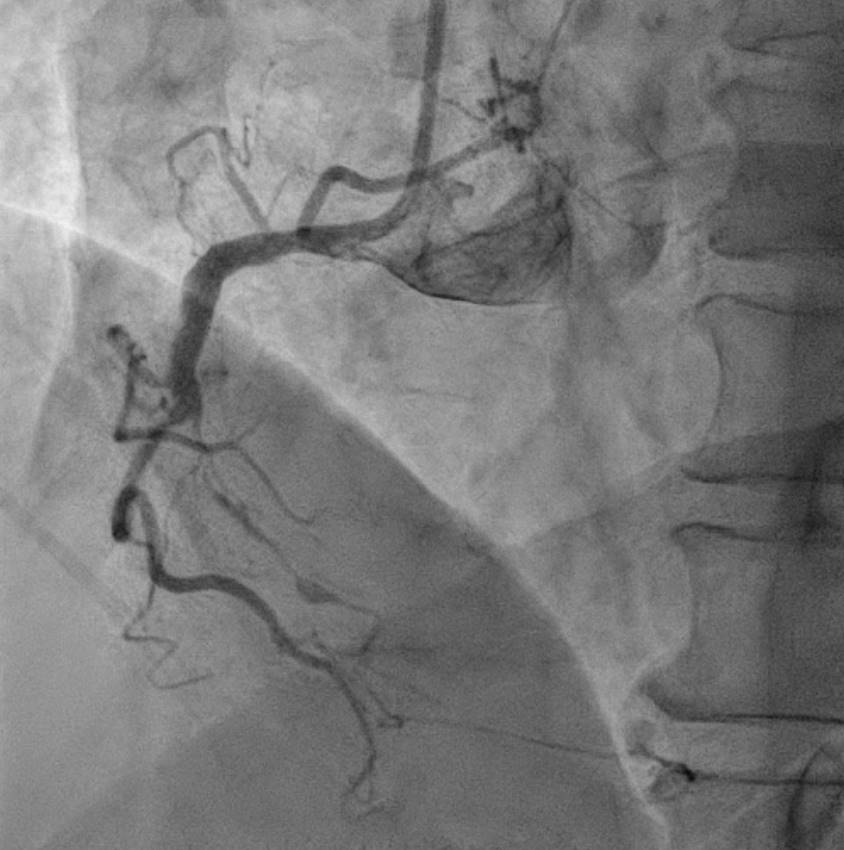

Coronary angiograpgy showed an middle RCA CTO, with septal collateral from LAD to PDA. The patient underwent an unsuccessful PCI attempt about one month before the index procedure, via RCA antegrade approach. However, due to persistent symptoms, he asked for second opinion and was admitted for another PCI attempt. Our strategy started with dual injection, The JCTO was 3 with long lesion, calcification, and re-attempt. We engaged RCA using AL1 guiding catheter, and LCA using EBU guiding catheter.